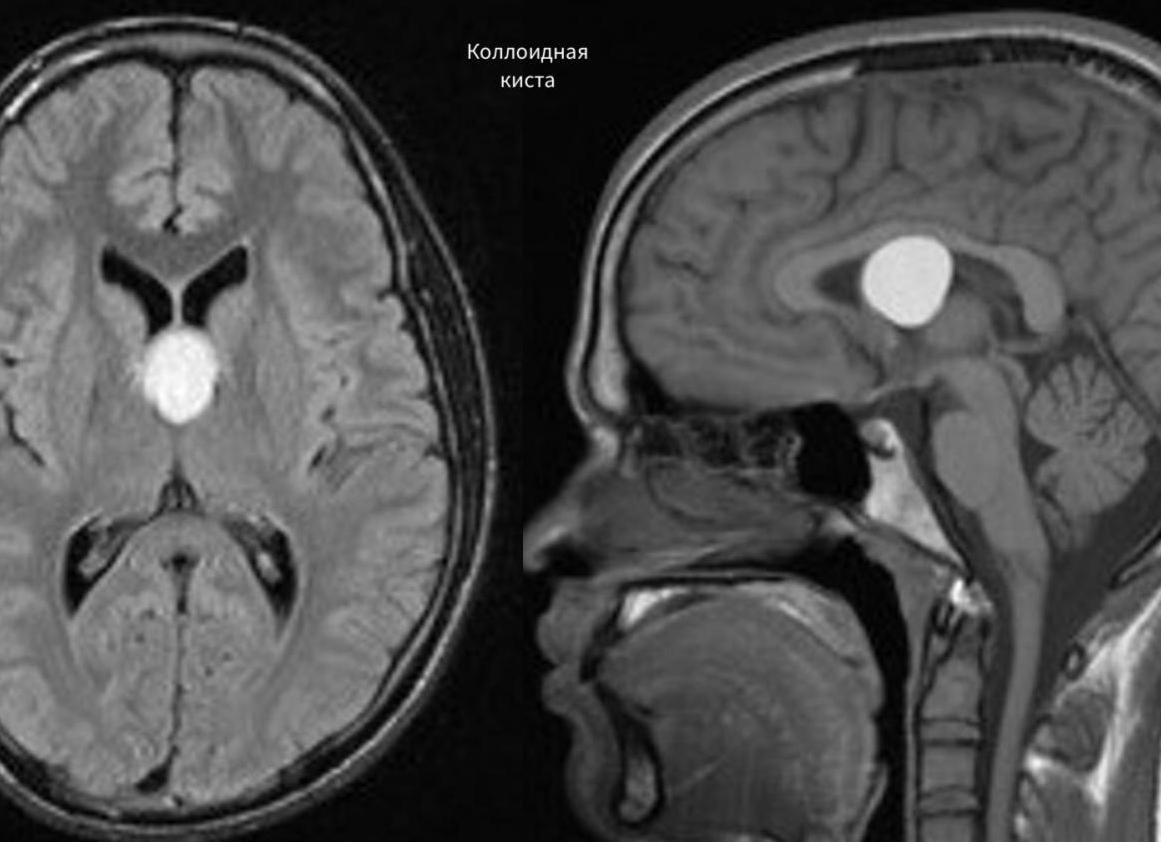

- Коллоидальная киста – протекает часто без каких-либо признаков, но при этом увеличивается в размерах. Когда размеры достигают критического уровня, прекращается отток ликвора, развивается гидроцефалия. Тогда хирургическое вмешательство является неизбежным и срочным;

Попов П.Р., нейрохирург. У одного из пациентов в полости третьего желудочка сформировалась коллоидная киста. Она перекрыла каналы оттока ликвора из других желудочков в третий и четвёртый желудочки головного мозга.

Кризис наметился в том, что возникла гидроцефалия. Это угроза для жизни.

Кроме этого, трудность в лечении представлял тот факт, что пациент потерял память. Такая ситуация сразу наводит на мысль о том, что киста давит на своды головного мозга и её нужно удалять.

Операция по удалению коллоидной кисты весьма сложная вещь, поскольку нужно всё время контролировать, чтобы жидкость из полости кисты никуда больше не попала, иначе начнётся инфицирование соседних желудочков. Это эндоскопическая малотравматичная операция.

Во время операции стенку коллоидной кисты не удалось удалить без последствий: открылось кровотечение, сформировалась гематома, поэтому пришлось удалять не только саму жидкость из кисты, но и гематому.

Удалять стенки кисты не обязательно, поскольку это может привести к негативным последствиям.

Коллоидальная киста.

Эта киста локализуется в третьем желудочке головного мозга и представляет собой полость из нейроэпителиальных или эндодермальных клеток, заполненную густой желеподобной жидкостью. Такая киста является врожденной, образуется в результате мутации, которая передается по наследству. Обычно имеет небольшие размеры и не угрожает здоровью человека.

Коллоидальная киста, локализованная в третьем желудочке головного мозга.